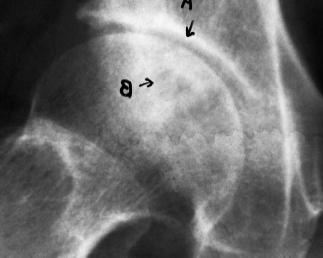

病例2,66岁,患病8年,治愈16个月修复。治疗前股骨头平坦,关节面粗糙,间隙消失,密度不均,有椭圆形死骨量(a)。进食后,关节间隙出现,关节表面光滑,骨密度恢复(b)

Case 2, 66 years old, 8 years sick, 16 months cured. Before eating, the femoral head was flat, the articular surface was rough, the space disappeared, the density was uneven, there were oval dead bone mass (a). After eating, the joint space appeared, the joint surface was smooth, and the bone density recovered (b)